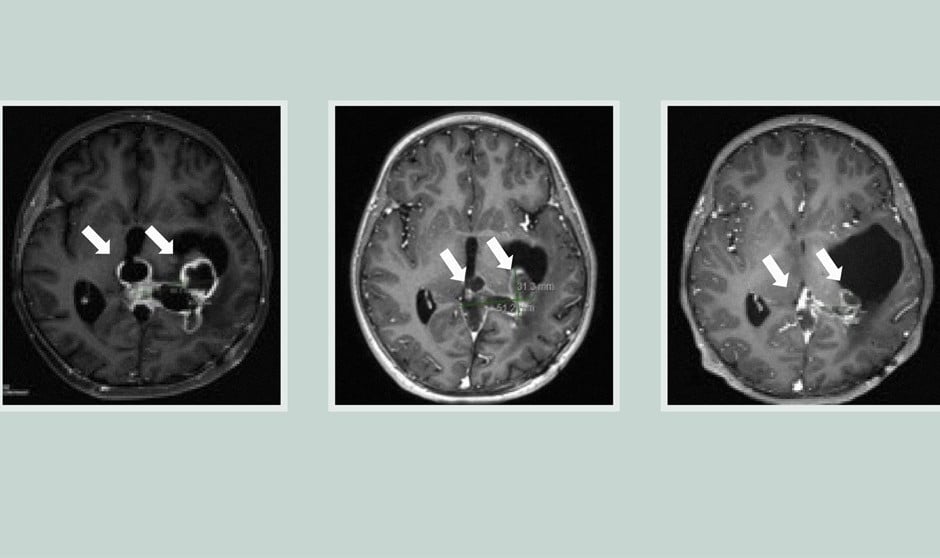

Los gliomas difusos de la línea media, incluidos los DIPG con una mutación denominada H3K27M, son particularmente agresivos, con una tasa de supervivencia global de 11-15 meses. Estos tumores son más frecuentes en niños y adultos jóvenes. El único tratamiento disponible es la radiación, e incluso eso es difícil ya que los tumores están situados en medio de regiones cerebrales con funciones críticas.

En dos ensayos clínicos en los que se probó el compuesto ONC201 en un total de 71 pacientes con gliomas difusos de la línea media mutados con H3K27M, la mediana de supervivencia global fue de casi 22 meses para los tumores que no habían recidivado en el momento de la inscripción. Casi un tercio de los pacientes vivió más de dos años.

El ONC201 siguió un camino poco habitual hasta llegar a los ensayos clínicos. Diseñado inicialmente para actuar sobre los receptores de dopamina, que están regulados al alza en muchos tumores diferentes, los investigadores vieron que el fármaco atravesaba la barrera hematoencefálica, uno de los mayores retos a la hora de diseñar fármacos para tumores cerebrales. Los ensayos iniciales en glioblastoma no tuvieron éxito, pero un pequeño número de pacientes con DMG portadores de la mutación H3K27M obtuvo resultados más prometedores. Sin entender por qué funcionaba mejor en estos pacientes, se inició un ensayo de fase 1 en niños y adultos jóvenes con DMG con mutación H3K27M.